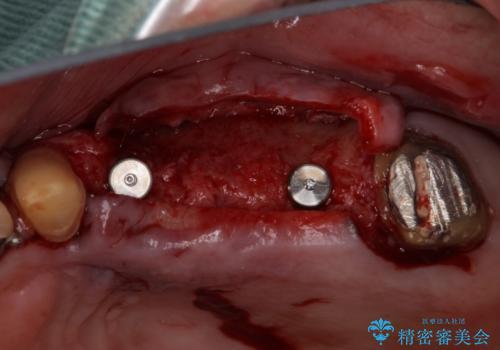

インプラントを埋入するために必要な骨の高さがなかったため、上顎洞底の粘膜を挙上しました。

手術後は処置部に痣や腫脹が出現したり、痛みが出たりしましたが、補綴治療後は咬み合わせが安定し、大変満足していただきました。